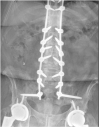

Sacropelvic is a complex junctional area owing to the complex regional anatomy and higher biomechanical stress. However extension of construct is indicated in cases with complex deformities, high grade spondylolisthesis, and complex fractures. The challenges remain which includes pseudoarthrosis and fixation failures. The fixation techniques have constantly evolved over time with better results with iliac screws and S2-alar-iliac screws. This article gives background on evolution, biomechanics, and recent update of use of robotics for sacropelvic fixation.